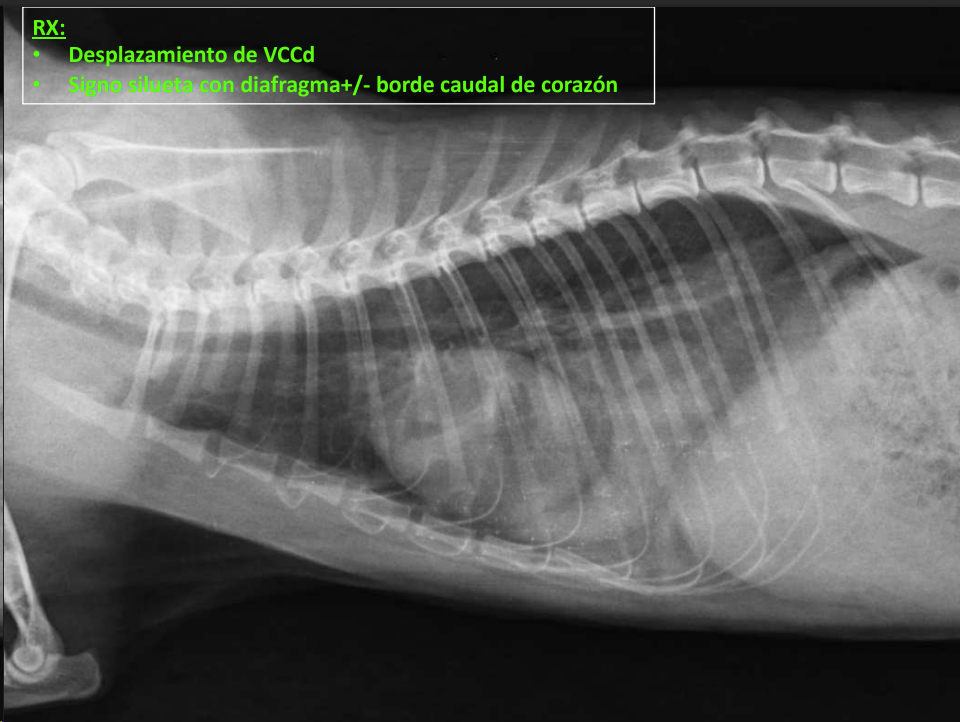

- Alteraciones de posición del mediastino (Desplazamiento mediastino VD)

- Vena cava caudal: diámetro ≈ aorta.